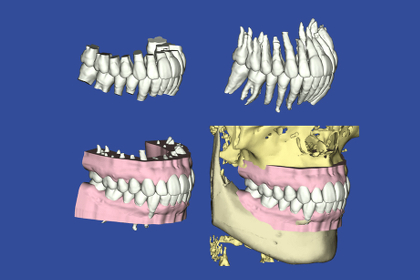

あなたのお口の中の3Dモデルを作成し、それを元に治療計画を立てます。そしてマウスピース型の矯正装置をこのように段階的に設計していきます。

矯正治療をご希望のすべての方には、治療結果の歯列をモニター上で確認できる「outcome simulator(アウトカムシミュレーター)」をお受け頂けるなど、より患者様に分かりやすい治療のご提案をしています。

日本橋はやし矯正歯科では、3Dデジタル矯正システムを応用した

マウスピース矯正での治療が可能となりました。